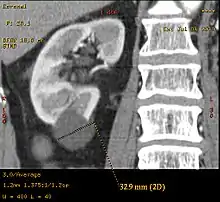

Bosniak II cyst at the lower pole of right kidney with septations within.